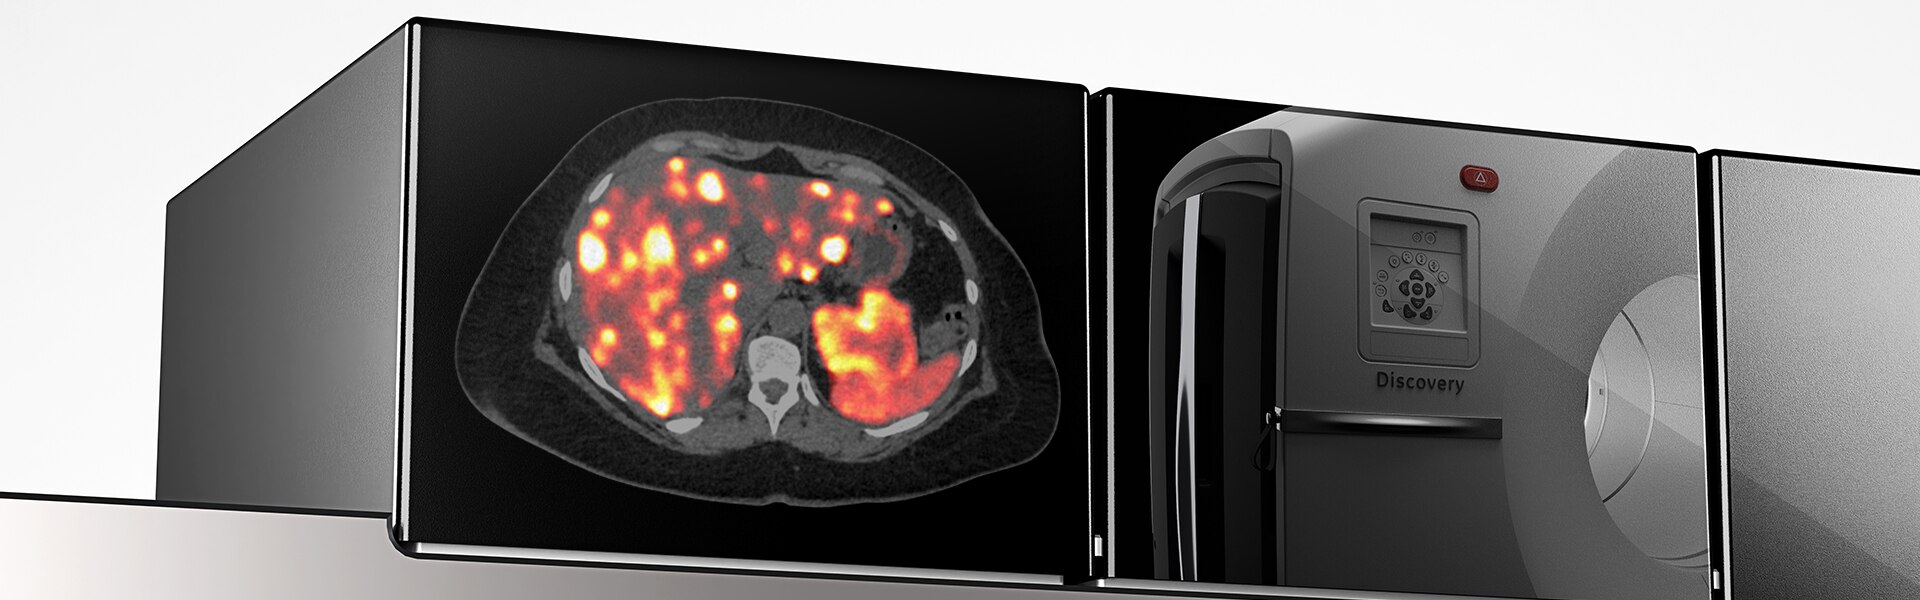

Güvenilir tedavi için doğru veri noktaları

- Görüntü kalitesinde 2 kata kadar iyileştirme (SNR)

- Kantitatif SUV'da (SUVmean) 2 kata kadar iyileştirme